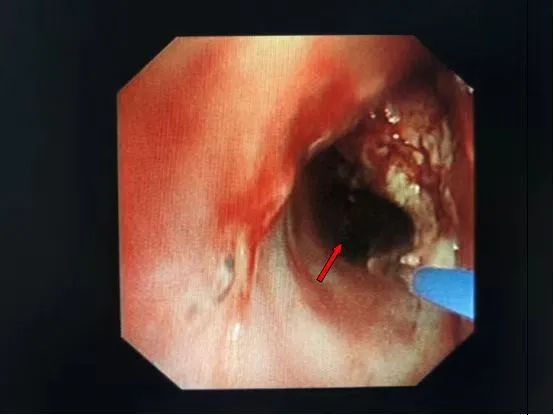

气管镜(术前):右主支气管及中间支气管新生物,堵塞大部分管腔

经过术前充分准备,罗少华主任带领气管镜室团队在表面麻醉下为患者行经支气管镜激光消融术,气管镜下见右中间支气管新生物堵塞管腔,行激光消融,仅半个小时就清除了管腔内大部分肿瘤组织,手术实施过程顺利,右中间支气管恢复畅通。术后患者呼吸困难明显缓解,复查胸片右中下肺叶复张,患者恢复良好,已出院。

气管镜(术后):右主支气管及中间支气管管腔内大部分肿瘤组织被清除